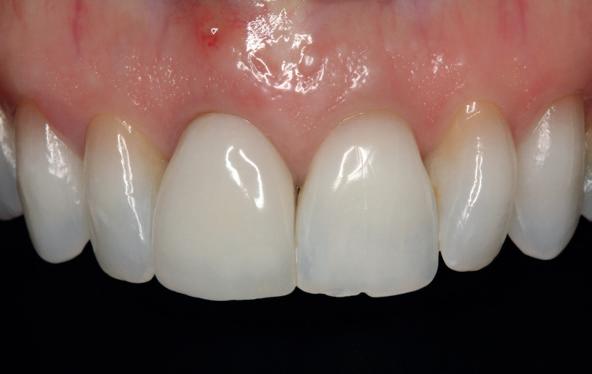

Implantologische behandelingen in het esthetische front vragen meer dan technische vaardigheid alleen. Ze vragen om overzicht, timing, vertrouwen en een team dat als vanzelf samenwerkt onder druk. Juist bij complexe casussen, waarin angst, infectie en hoge esthetische verwachtingen samenkomen, wordt zichtbaar hoe bepalend de rol van de tandartsassistent is.

Deze casus beschrijft een uitgebreide immediate implantaatbehandeling bij een patiënt die door meerdere collega’s werd geweigerd. Niet omdat de mogelijkheden ontbraken, maar omdat de complexiteit vroeg om een perfect afgestemde samenwerking. Het verhaal laat zien hoe de assistent in zo’n traject veel meer is dan een uitvoerende kracht of “mal”, maar een dynamische surgical guide die het proces mede stuurt, bewaakt en mogelijk maakt.De patiënt: wanneer alles samenkomt

De kern van haar vraag was eenvoudig en tegelijkertijd uitdagend: Is het mogelijk om mijn huidige brug te dupliceren en een nieuwe brug te vervaardigen met minder complicaties?

Na het klinische onderzoek volgde het röntgenologisch traject. De CBCT liet precies zien wat we al vreesden: een front waarin het bot onregelmatig was, duidelijke radiolucenties rond de pijlers en een infectiegebied dat zich onder vrijwel de gehele brug had verspreid. Tegelijkertijd was er ook potentie. Net voldoende botstructuur om immediate implantaatplaatsing te overwegen, mits alles perfect gepland zou worden.